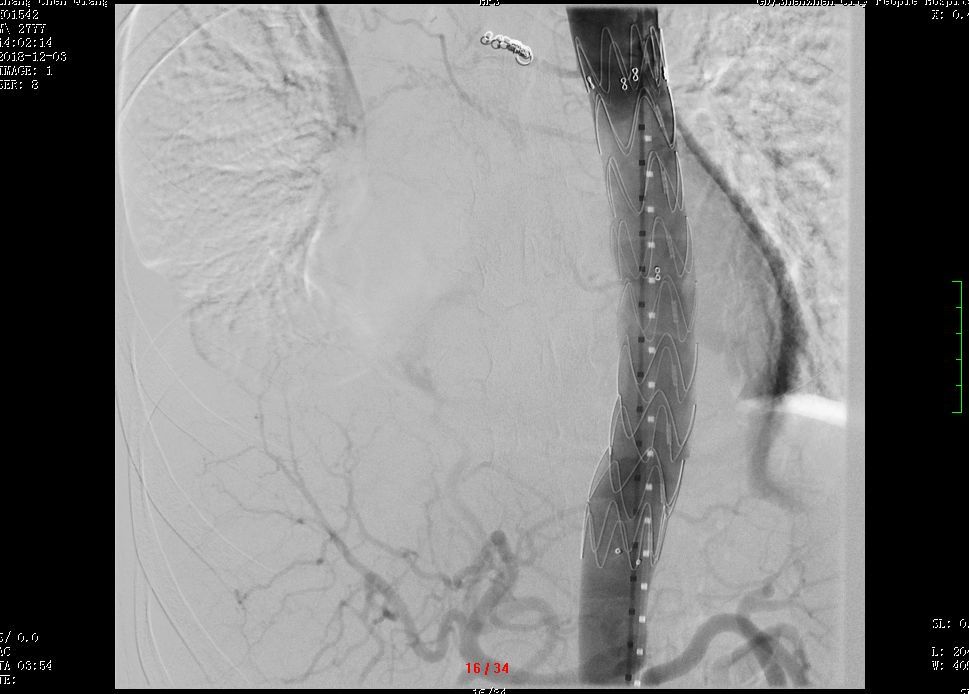

完善术前准备后,2018年12月6日9:40,深圳市人民医院心外科主任郑齐军团队为张先生实施了插管麻醉下行升主动脉替换+全主动脉弓置换术+降主动脉覆膜支架置入术。

本次手术首次采用胸骨上段小切口,长约15cm。小切口对于患者来说损伤小,术后恢复快,但对术者来说要求却非常高。

在如此小的视野中要完成头臂干、左颈总动脉及左锁骨下动脉的游离;并要完成主动脉根部、远端及三大分支的人工血管和自身血管的端端吻合,实现全主动脉弓人工血管置换。术中脑灌注是最关键的问题,直接关系到病人的预后。因此,就要求术者在极小的手术视野中,花费和常规切口同样的时间内完成手术操作,难度极大。

在计时器的滴答声中,心外科手术团队争分夺秒,短时间内顺利完成了深圳市人民医院首例小切口下全主动脉弓置换术。整个手术过程顺利,张先生安返病房,未再出现咯血。